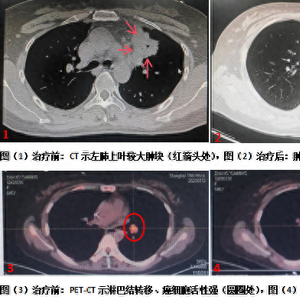

治疗前后,影像学检查对比图。 本文图均为 上海市第四人民医院 供图

治疗前后,影像学检查对比图。

经过一年的治疗,疗效显著。张女士曾经的疼痛感都消失了,目前日常生活与健康人无异。PET-CT检查显示,其癌症原发灶被灭活,局部转移灶肺门淋巴结和远处转移病灶(髂骨转移)癌细胞活性明显被抑制,病灶显著缩小,整体癌症治疗获得了绝大部分缓解。